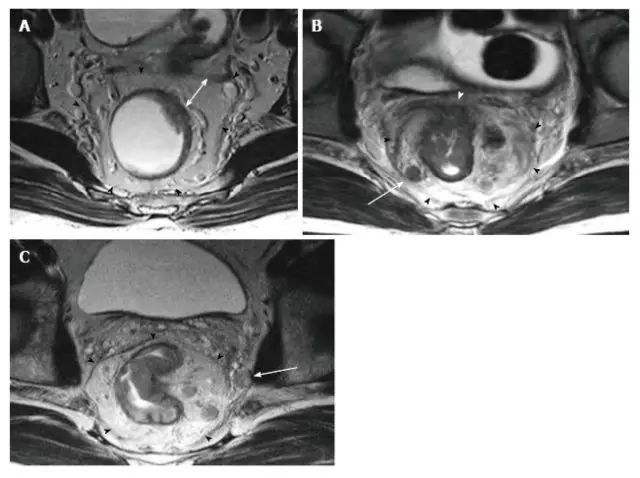

表 1 和图 14、图 15 显示了如何鉴别肿瘤 T 分期和环周切缘(CRM)。

图 14. 根据低直肠癌的每个阶段的示意图和高分辨率冠状 T2 加权磁共振图像。不同患者的直肠肿瘤用磁共振图像上的箭头表示。

图 15. Ⅳ 期低位直肠癌。

在 T2 加权(A)冠状面(B,C)轴向磁共振图像显示,直肠癌浸润提肌(红色箭头)和直肠系膜筋膜(白色箭头)。

LA:肛提肌;PR:耻骨直肠肌;MRF:直肠系膜筋膜;BL:膀胱;V:阴道。